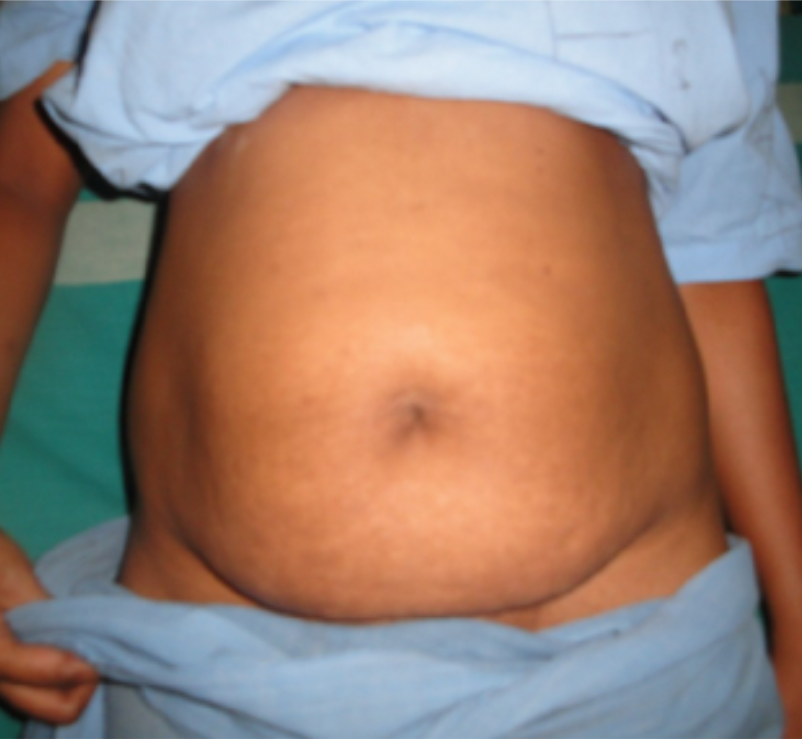

ABDOMINOPLASTY